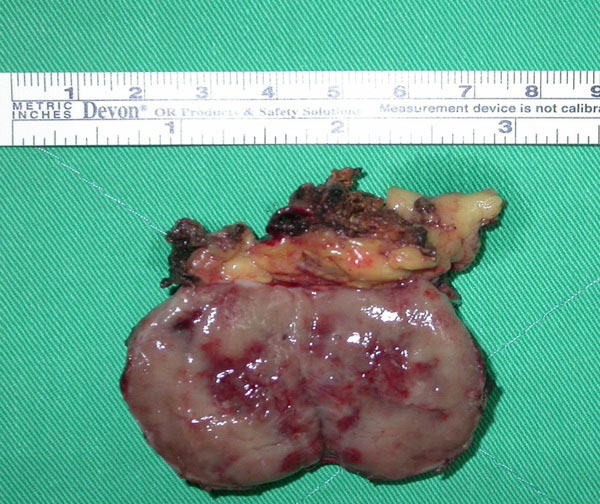

The tumor was removed completely with laparoscopy. Fig. (4) shows the resected tumor. The total operation time was 300 mins. Estimated blood loss was 300ml. The patient had an uneventful postoperative course and was discharged after 6 days.

Photograph of the resected specimen consisting of an encapsulated tumor (T) sized in 3.5x3x3 cm, associated with an adrenal gland (A).

Pathology confirmed the diagnosis of paraganglioma. The specimen consisted of an encapsulated tumor, associated with adrenal gland. The tumor with adrenal gland weighed 24gm and measured 3.5x3x3cm (Fig. 4). The tumor was composed of chromaffin cells with granular and basophilic to amphophilic cytoplasm in a predominantly alveolar (zellballen) growth pattern. There was prominent cellular and nuclear pleomorphism (Fig. 5A, 5A). Immunohistochemistry revealed that the tumor cells were strongly positive to chromogranin A (Fig. 5c). S-100 protein was detected by the supportive cells that surround the nests (Fig. 5D).These findings are consistent with paraganglioma. The stroma was vascular-rich and with focal sclerotic changes. There were rare mitotic figures. No adrenal cortical tissue was observed in the tumor. The tumor was separated by adipose tissue from the adjacent adrenal gland with a well defined fibrous capsule.